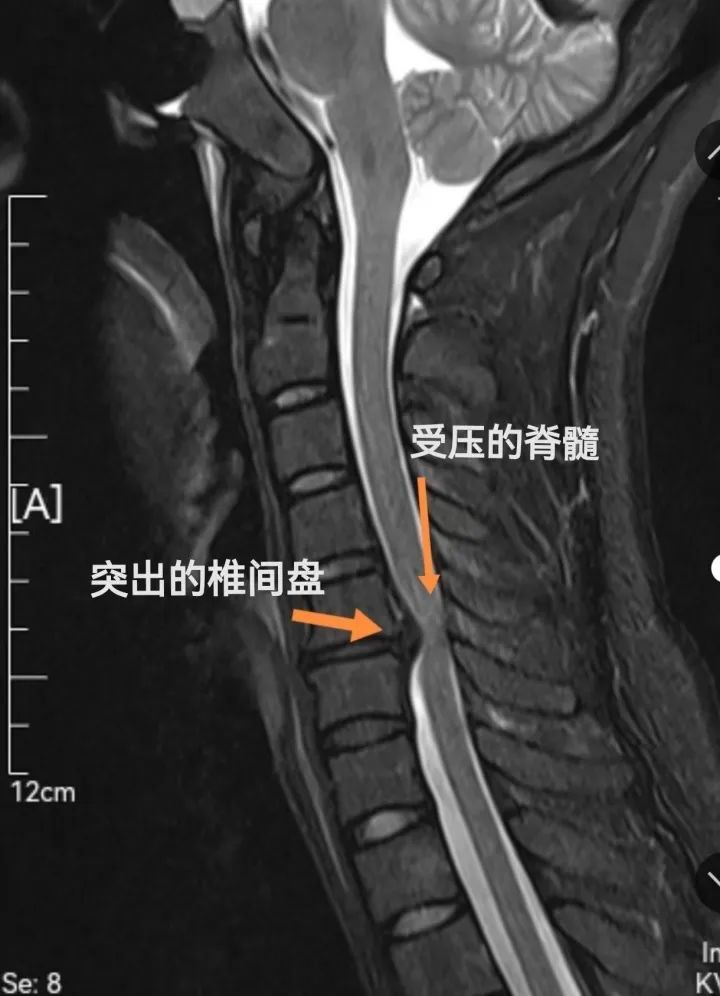

1、长期低头可能引起颈椎问题,如僵硬和疼痛。 2、为保护颈椎,应保持正确姿势,减少连续使用电子设备时间,并定期做颈部锻炼。 3、如出现肩颈疼痛或其他颈椎不适,请及时就医并采取相应的预防和治疗措施。 当头部和颈部长时间保持前屈姿势时,颈椎不仅要支撑头部重量,还要承受头部和胸部肌肉的牵拉力,头部每向前伸出2.5厘米,颈椎所受的压力可能增加一倍。长时间承受这种增加的压力,可能导致颈椎出现僵硬感、颈椎间隙变窄、生理曲度减少,以及轻度骨质增生等问题。 导致肩颈肌肉紧张和疼痛 低头使用手机时,上斜方肌、竖脊肌和颈伸肌为了支撑头部重量会持续处于紧张状态。这种持续的紧张可能引起肌肉、筋膜和韧带的过度拉伸,进而导致肌肉疲劳、颈部活动受限和疼痛。严重时,疼痛可能放射至背部、肩部和上肢,甚至引发肌肉痉挛。 影响颈部的血液循环 颈部血管受到挤压,血液流动受限,可能引起头痛、眩晕、注意力不集中,甚至视力模糊等症状。 增加颈椎间盘压力 研究显示,人们在低头使用手机时,头部与垂直方向保持33-45°的弯曲。颈椎的自然曲线因此改变,使其处于非正常的位置,长时间保持这种姿势会导致颈椎间盘前部压力增加,髓核逐渐后移,引起颈椎间盘突出和变性。 脊髓型颈椎病(Cervical Spondylotic Myelopathy,CSM),顾名思义是指以脊髓受压为主要病变的一种颈椎病,通常是由于颈椎退变、老化导致的。脊髓是非常重要的中枢神经,同时也是临近颈椎的主要结构,因此CSM是各种类型的颈椎病中最严重和最常见的。 CSM的主要临床症状 如果CSM一直不治疗,病情会有什么样的演变呢? 可预测的结果:病情缓慢进展,但无法逆转 早在1956年,两位英国医生就曾经对120名CSM病人进行过长期观察(PMID: 13364095)。在平均长达3年的观察期内,这些病人出现了下面三种情况: 01 症状进展 02 症状稳定 03 长时间稳定后快速恶化 减少低头时间:限制手机的使用时长,每半小时到三刻钟时停止低头,抬头看看窗外。 保持正确姿势:在使用手机时,可以借助支撑工具,如手机支架,将屏幕调整至眼睛水平线的高度,以维持头部和颈部的自然姿态,并减少低头的频率。 适度锻炼:日常可进行颈部和肩部的运动,以增强颈椎稳定性和肩颈部位肌肉的力量。 颈椎操 建议每个动作重复8-10次,每次运动5-10分钟。 注意:如果已经出现肩颈疼痛或其他颈椎问题,应提高重视,及时就医,尽早采取预防或治疗措施。 不用手机是做不到的,但通过采取适当的措施,我们可以减轻低头对颈椎的潜在危害,千万别等到问题严重了,才想到要补救。长期低头使用其他电子设备也要注意这个问题哦! 编辑 / 宗哲麟 资料 / 上海仁济医院 上海疾控 转载请注明来自上海黄浦官方微信